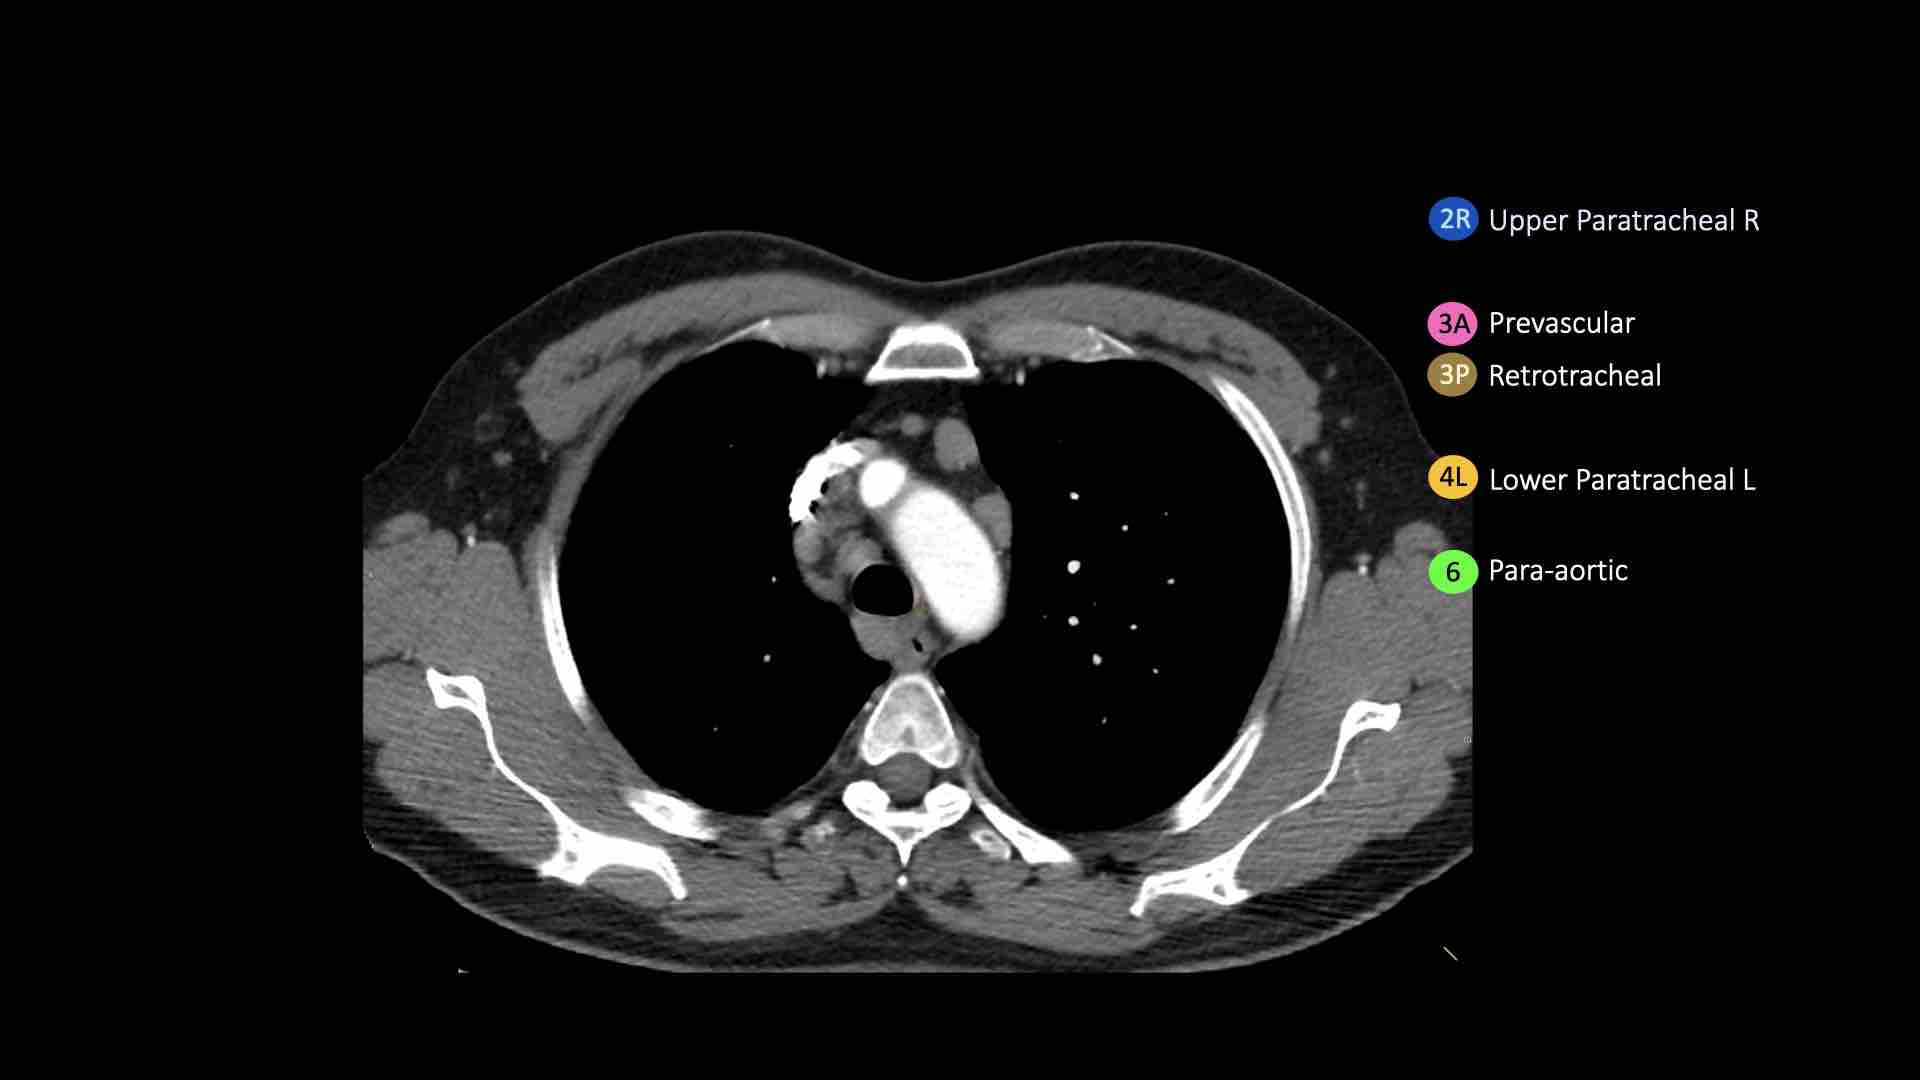

4R.Cạnh khí quản dưới

Từ điểm giao nhau giữa bờ dưới tĩnh mạch vô danh (tĩnh mạch tay đầu trái) với khí quản đến bờ dưới tĩnh mạch đơn.

Hạch nhóm 4R trải dài từ bờ bên phải đến bờ bên trái của khí quản.

4L.Cạnh khí quản dưới

Từ bờ trên của quai động mạch chủ đến bờ trên của động mạch phổi trái.

Hạch động mạch chủ nhóm 5-6

6. Cạnh động mạch chủ

Đây là các hạch của động mạch chủ lên hoặc hạch cơ hoành, nằm ở phía trước và bên của động mạch chủ lên và quai động mạch chủ.

4R. Hạch cạnh khí quản dưới bên phải

Ranh giới trên: giao điểm của bờ dưới tĩnh mạch vô danh (tĩnh mạch tay đầu trái) với khí quản.

Ranh giới dưới: bờ dưới tĩnh mạch đơn.

Hạch nhóm 4R trải dài đến bờ bên trái của khí quản.

Bên trái là hạch cạnh khí quản 4R.

Ngoài ra còn có một hạch động mạch chủ nằm bên ngoài quai động mạch chủ, tức là hạch nhóm 6.

4L. Hạch cạnh khí quản dưới bên trái

Hạch nhóm 4L là các hạch cạnh khí quản dưới nằm bên trái bờ trái của khí quản, giữa đường nằm ngang tiếp tuyến với bờ trên quai động mạch chủ và đường tiếp tuyến với bờ trên động mạch phổi trái.

Nhóm này bao gồm các hạch cạnh khí quản nằm ở phía trong dây chằng động mạch.

Hạch nhóm 5 (cửa sổ phế động mạch) nằm ở phía ngoài dây chằng động mạch.

6. Hạch cạnh động mạch chủ

Hạch cạnh động mạch chủ (động mạch chủ lên hoặc cơ hoành) nằm ở phía trước và bên ngoài động mạch chủ lên và quai động mạch chủ, từ bờ trên đến bờ dưới của quai động mạch chủ.

- Cạnh khí quản dưới: từ bờ trên cung động mạch chủ xuống đến mức phế quản gốc

- Dưới động mạch chủ (cửa sổ A-P): các hạch bạch huyết nằm bên ngoài dây chằng động mạch hoặc bên ngoài động mạch chủ hay động mạch phổi trái

- Cạnh động mạch chủ: các hạch bạch huyết nằm ở phía trước và bên ngoài động mạch chủ lên và cung động mạch chủ, bên dưới bờ trên của cung động mạch chủ